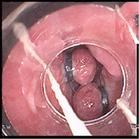

②结肠镜

结肠镜可以观察包括直肠、乙状结肠、降结肠、 横结肠、升结肠、盲肠至回肠末端的肠道黏膜,主要用于诊断结、直肠炎症,良性肿瘤,息肉,憩室等疾病